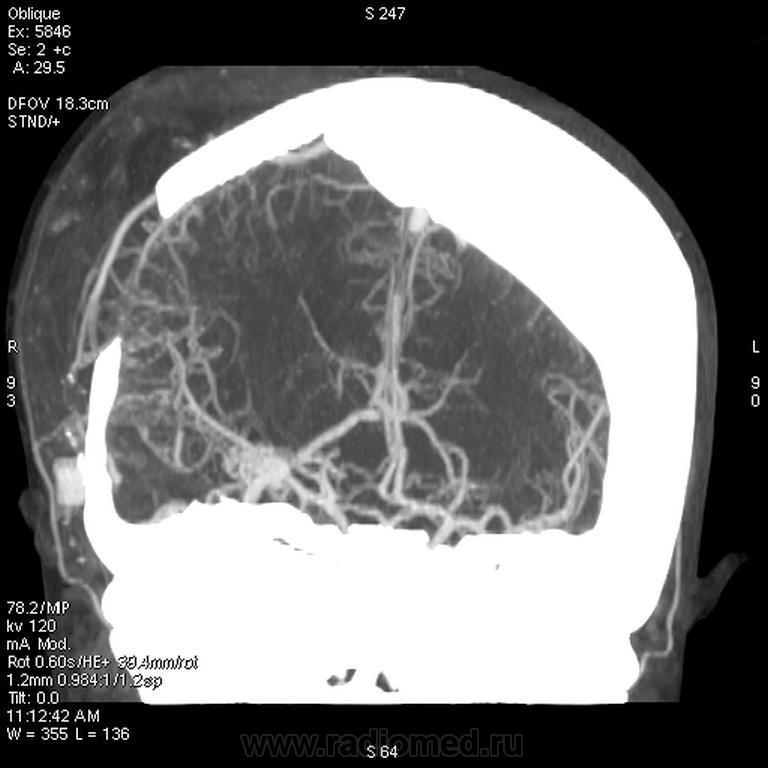

Хочу поделиться наблюдением. Поступила девушка 19 лет в ухудшением по поводу кровоизлияния в области сильвиевой щели справа вследствие АВМ. Повторное сканирование показало, что вновь кровоизлияние из узла... Предыдущее было пару месяцев назад. Делается прямая ангиография для изучения расположения клубка патологических сосудов для его оперативного выделения и удаления. Сделали - результат не утешительный, правая средняя мозговая артерия четко не визуализируется и принадлежность её к АВМ достоверно определить не удалось. Делаем КТ-ангиографию...

вот обработочка в искривленных плоскостях... Правая СМА не вовлечена, на прямой ангиографии не видно этого, даже постфактум. Нейрохирурги уверенно идут на операцию и очень тщательно выделяют её, убирая клубок. Операция прошла успешно, благодаря мастерству и решительности наших хирургов.

прямая агниография через бедренную артерию, в т.ч. селективная. Возможно, схожу принесу снимки и оборотную 3Д. Во всех проекциях - клубок сосудов, накладывающихся друг на друга, равномерно и своевременно заполняющихся контрастным препаратом вместе с СМА. Все сосуды тесно прилежат друг к другу. На этот случай я лично с нейрохирургами ходил в кабинет ангиографии и смотрел. Никто из нас не понял четко... КТ-ангиография разрешила всё.